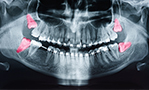

歯の移植は、奥歯に抜く際に必要ない(かみ合わせに関係していない)親知らずが残っていて、それが割ったり、削ったりすることなく抜ける状態にあることが必要です。

場合にもよりますが、抜かないといけない奥歯を抜き、それと同時に親しらずを抜き、はじめに抜いた奥歯の場所へ植えなおすことが出来ます。

この処置を行った場合、喫煙をされていない方が良いなど、多少の条件が加味されますが、当院の処置例から考察しますと、比較的高い確率で、移植した歯は機能(きちんと定着)します。

臼歯が1本失われたとき

健康な親知らず(智歯(ちし))があれば、それを利用します。

例えば、右下の6番目の歯が抜けてしまったとします。

そんな時は、条件がそろえば奥歯の後ろに埋まっている智歯を取り出して移植し、奥歯の代わりにします。